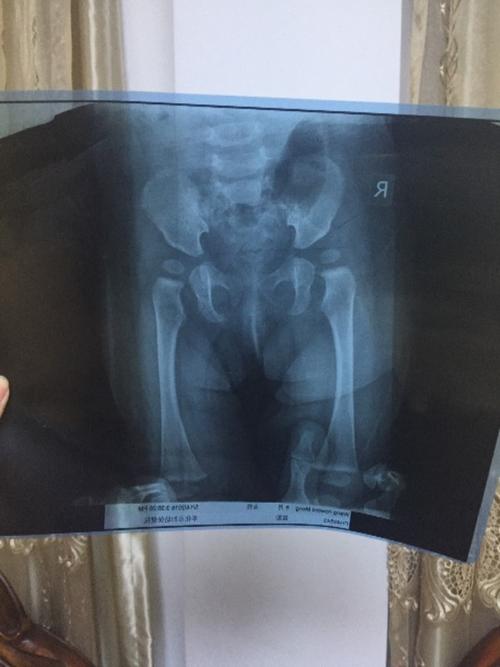

宝宝八个月拍片医生说髋关节发育不良,帮忙看下图片,谢谢,需要带支

易误诊的骨盆假性骨折:正常骺线

骨盆正常图像,大骨盆小骨盆

大骨盆小骨盆